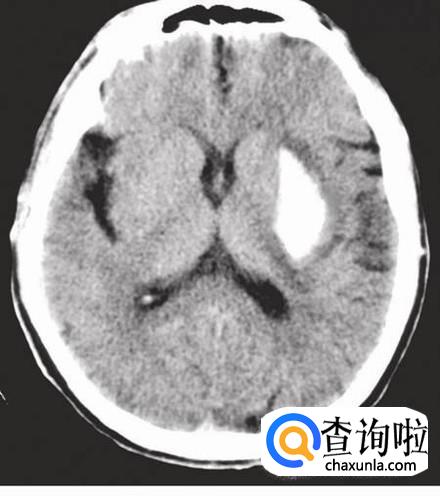

当一个人大脑皮层功能严重损害,这个人就会处于不可逆的深昏迷状态,丧失意识活动,但可维持自主呼吸运动和心跳,此种状态称“植物状态”,处于此种状态的患者称“植物人”。

长时间的大脑缺氧就会导致大脑皮层受损,如果大脑受损严重,就有可能导致变成植物人。如溺水,窒息。

持续性低血压发作脑血管意外,如脑出血、脑梗死、蛛网膜下腔出血等,也会导致变成植物人。